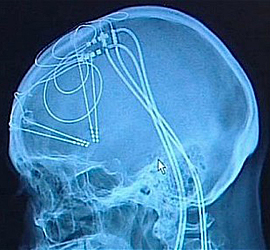

DBS, or Deep Brain Stimulation: we’ve heard of it, but what the hell is it? Can placing electrodes in your brain really fight the forces driving addiction? DBS is a surgical procedure performed under general anesthesia, after MRI scans have identified a target in the brain. A small area of the scalp is removed, and a probe places an electrode at the desired location. Mild electrical impulses then stimulate the area in question. A recent article in the journal Addiction calls for well-controlled clinical trials of DBS for addiction, despite the substantial risks involved.

To date, DBS has been employed mainly as a controversial treatment for Parkinson’s disease and epilepsy. It was first used in the US in 1997 by neurosurgeons at the Mayo Clinic, and is now being considered for depression and OCD, as well as addiction. Studies on rats have shown that using DBS on a brain region called the subthalamus nucleus can influence cocaine dependence; but an earlier Addiction contributor argued that the scientific rationale for this was poor, and the clinical evidence unconvincing. The ultimate target is a tiny region known as the nucleus accumbens, where addictive drugs do much of their work.

Last year, some Chinese neurosurgeons horrified the world by actually destroying the nucleus accumbens in an attempt to “cure” addiction. DBS wouldn’t be as drastic, but the possible complications—like intracerebral hemorrhage, infection and emotional disturbances—are daunting. Still, a recent article in the journal Nature presents evidence that direct brain stimulation of the nucleus accumbens could lead to “reversal of cocaine-evoked synaptic plasticity,” which might lead to loss of interest in addictive drugs. The jury’s out.